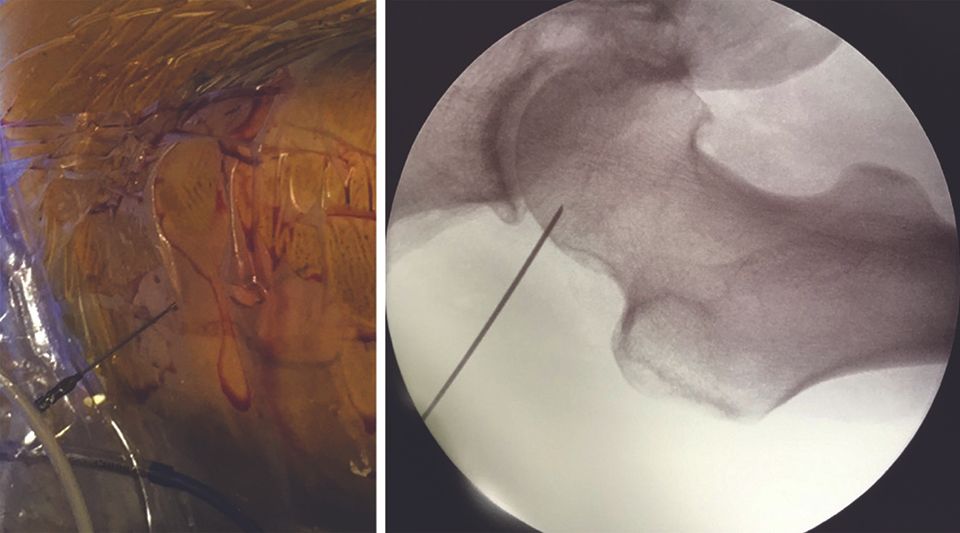

In my experience, the first point of entry is often situated mid-way between the ASIS and the apex of the greater trochanter (Fig. 13, left).

The needle is introduced, guided by the image intensifier, perpendicular to the superior part of the junction between the femoral head and neck (Fig. 13, right). Making small movements, the needle is used to probe along the lateral part of this junction to position it in the space between the anterior capsule and the anterior part of the junction between the femoral head and neck. Next, the nitinol guide is introduced, followed by the trocar for inserting the arthroscope.

The position of the lesser trochanter is noted in the image intensifier and the two portals are created along a vertical line, a little in front of the anterior rim of the femur, 3 cm either side of the lesser trochanter (Fig. 19).